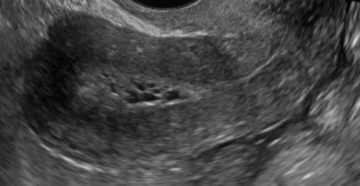

Гиперплазия эндометрия матки в менопаузу: что это такое, симптомы, причины, лечение Патология является следствием излишне…